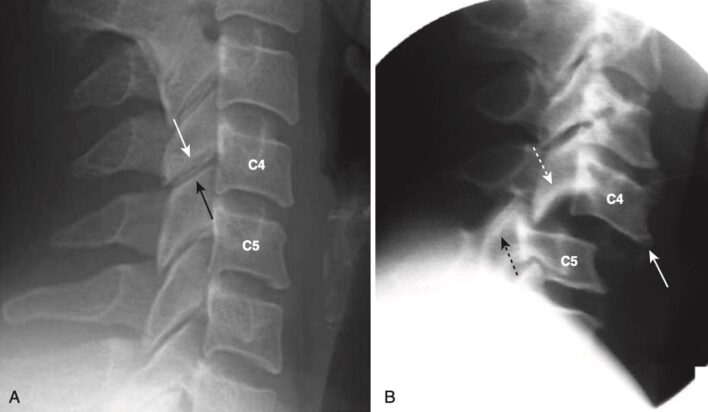

Locked facets (trật cài khớp diện nhỏ/liên mỏm)

- Trật cài khớp diện nhỏ hai bên ở cột sống cổ có thể xảy ra do một chấn thương gập quá mức (hyperflexion) trong đó các diện nhỏ dưới của một thân đốt sống trượt qua và ra trước các diện nhỏ trên của đốt sống bên dưới. Ở vị trí này, các mặt khớp bị trượt không thể trở lại vị trí bình thường nếu không can thiệp; vì thế được gọi là bị cài khoá (locked).

- Trật cài khớp diện nhỏ xảy ra khi có sự trượt ra phía trước của thân đốt sống phía trên lên phần thân đốt bên dưới ít nhất 50% đường kính trước sau (AP).

- Trên phim nghiêng cột sống cổ, mỏm khớp/diện nhỏ dưới (của đốt trên) nằm trước mỏm khớp trên (của đốt dưới), ngược với quan hệ giải phẫu bình thường giữa các mỏm khớp (Hình 18).

- Vì các mỏm khớp trên không còn được “che phủ” bởi các mỏm khớp dưới ở phía trên chúng, nên hình ảnh này trên CT được gọi là dấu hiệu mỏm khớp ở trần (naked facet sign).

- Tổn thương này hầu như luôn luôn dẫn đến khiếm khuyết thần kinh.